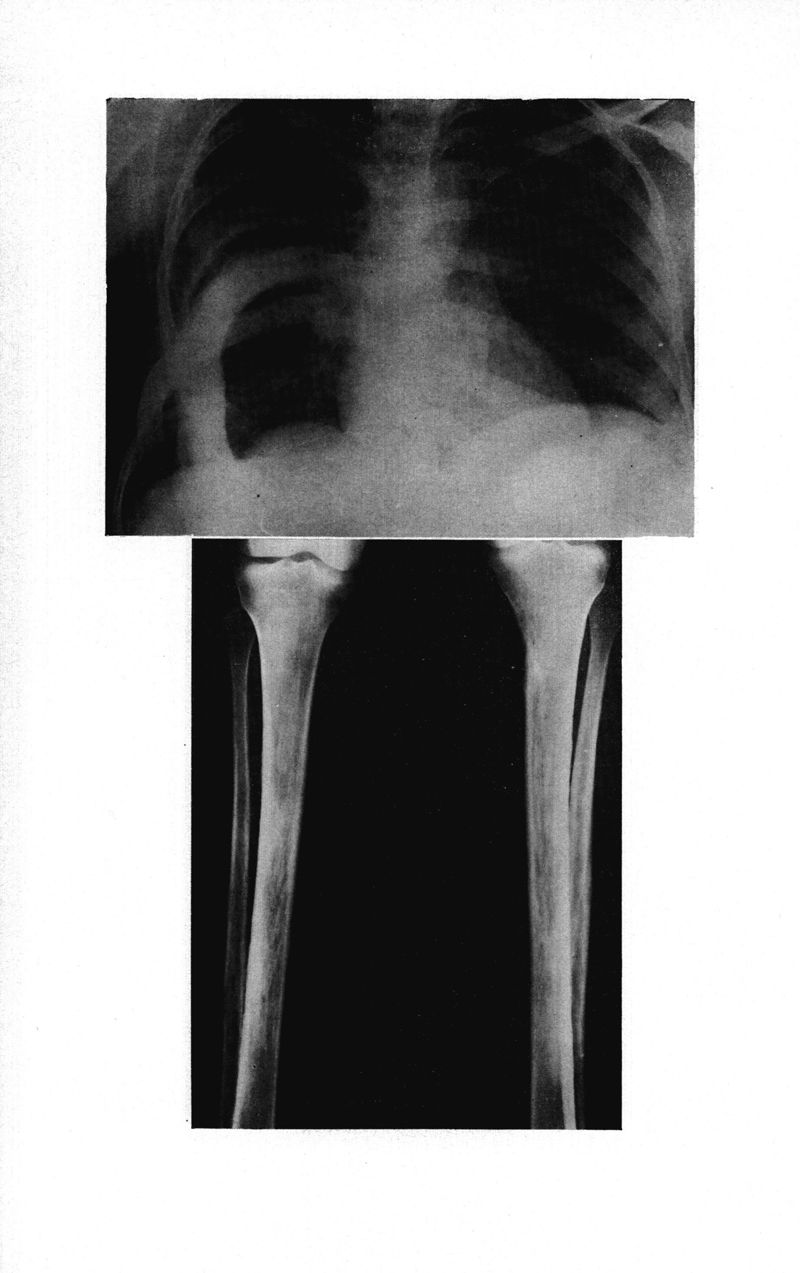

Médecine tropicale: revue française de pathologie et de santé publique tropicales

. - Marseille, 1974.